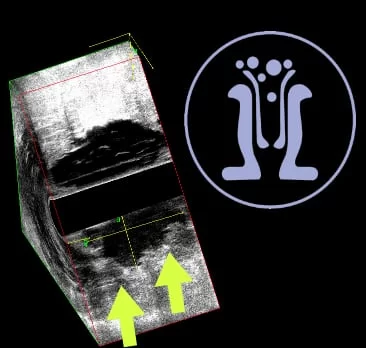

Ασθενής, 64 ετών, με ιστορικό παροχέτευσης περιεδρικού αποστήματος προ 2 εβδομάδες. Ο ασθενής ανέφερε επίσης έναρξη δυσκοιλιότητας και παρουσία αίματος στα κόπρανα από 3 μήνου. Το ενδοπρωκτικό υπερηχογράφημα έδειξε, από το δέρμα μέχρι τα στα 5-46 mm πάνω από το άνω όριο των σφιγκτήρων, διηθητική χωροκατακτητική εξεργασία πάχους 21 mm. Επιπροσθέτως, αυτή επεκτείνεται σαφώς στο περιορθικό λίπος και στο επίπεδο του πρωκτού διηθεί τον έξω σφιγκτήρα. Κάτω και στην 1η ώρα του πρωκτού ανευρέθηκε παροχετευμένο περιεδρικό απόστημα στο υπόβαθρο της διηθητικής επεξεργασίας. Συνεστήθη λήψη βιοψιών της εξεργασίας και κατόπιν ογκολογική συνεκτίμηση προ του χειρουργείου.